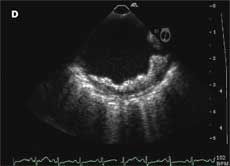

A previous transthoracic echocardiogram with a bubble study did not reveal any cardiac source of embolism. Axial MRI of the brain on admission showed an abnormal signal in the bilateral hemispheres representative of multiple subacute infarcts (Aand B); the right posterior frontal and right posterior parietal cortical and subcortical regions appeared to be most affected. A transesophageal echocardiogram revealed a severely thick atherosclerotic plaque with a large pedunculated mobile complex atheroma (C, arrow) in the upper descending aorta; the aortic arch showed severe atherosclerotic plaques with maximal thickness up to 10 mm (D).

Atherosclerotic plaques of 4 mm or greater in the aortic arch are significant predictors of recurrent brain infarctions. Transesophageal echocardiography should be considered for early detection in patients with an unidentified source of embolism.